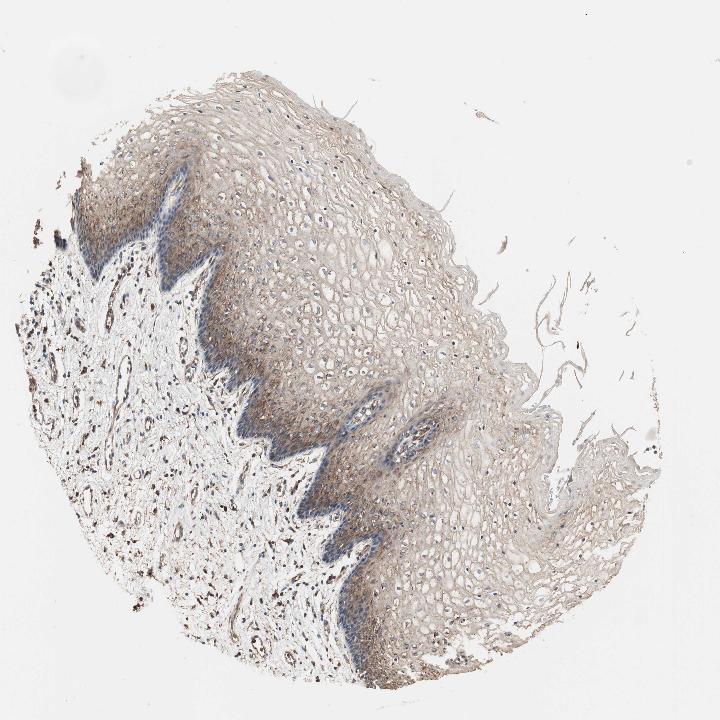

VAGINA - Antibody stainingi

Antibody staining in the annotated cell types in the current human tissue is reported as not detected, low, medium, or high, based on conventional immunohistochemistry profiling in selected tissues. This score is based on the combination of the staining intensity and fraction of stained cells.

Each image is clickable and will lead to virtual microscopy that enables deeper exploration of all samples and also displays staining intensity scores, fraction scores and subcellular localization as well as patient and tissue information for each sample.

Antibody HPA004824Antibody HPA005440

Squamous epithelial cells Not detectedMedium